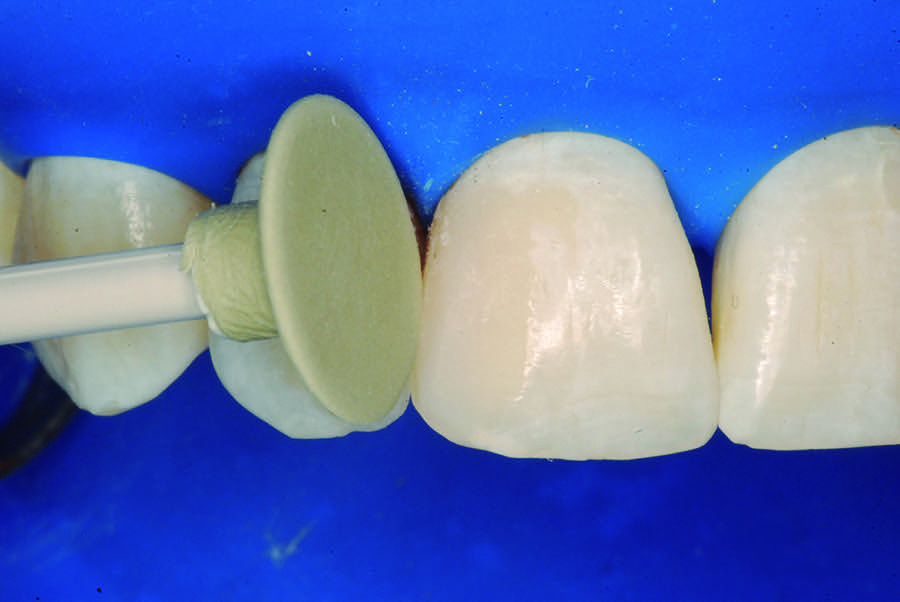

After 7 days, final finishing and polishing were performed using abrasive discs (Figure 16), multi-laminated burs, abrasive rubber points, and, finally, a felt disk with 40-μm diamond paste (Figure 17 and Figure 18). The results could be observed after 200 days (Figure 19), demonstrating the absence of a pathologic lesion in the apical region of the lateral incisor with an esthetic favorable condition, gingival health reestablishment, and pulp vitality maintenance.

Fig 17. Finishing with abrasive layers.

Figure 17

Fig 18. Final polishing with rubber points and felt disc.

Figure 18